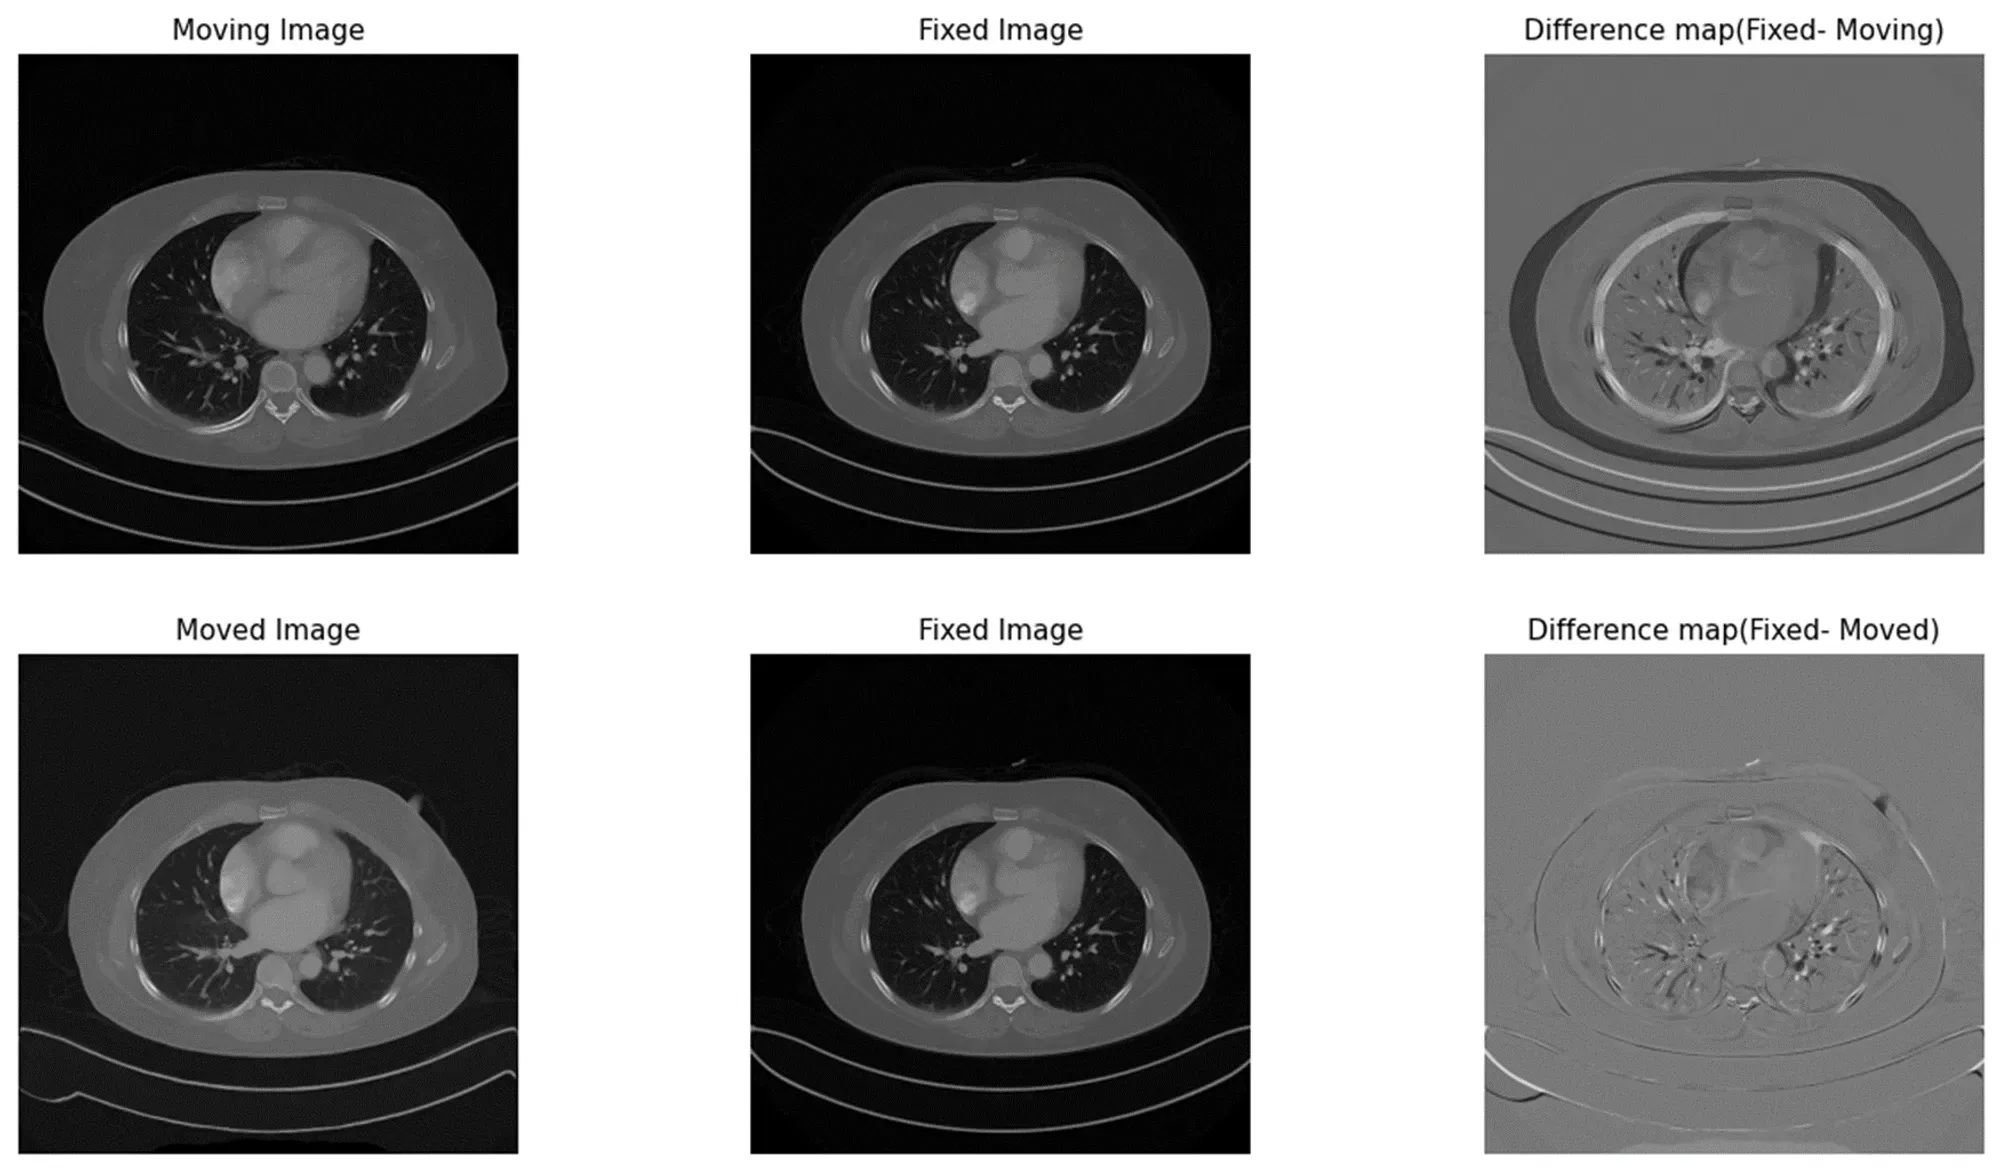

CT 데이터의 크기가 상당히 크기 때문에, 효율적인 학습을 위해서 Patch 기반으로 접근 방식을 채택하였습니다. 위 그림의 경우 폐 정합 모델을 통해서 정합 대상 이미지가 정합된 이미지가 된 결과입니다.

상단 가장 오른쪽에 위치해있는 Difference map을 보게 되면 정합되기 이전인 정합 대상 이미지와 정합 기준 이미지 간의 폐의 크기와 바깥 몸의 부피 위치 차가 상당히 크게 나는 것을 확인 할 수 있습니다.

하지만 하단의 가장 오른쪽 위치해있는 Difference map을 확인하면, 크기와 몸의 부피의 차이가 확연하게 줄어든 것을 확인 할 수 있습니다.